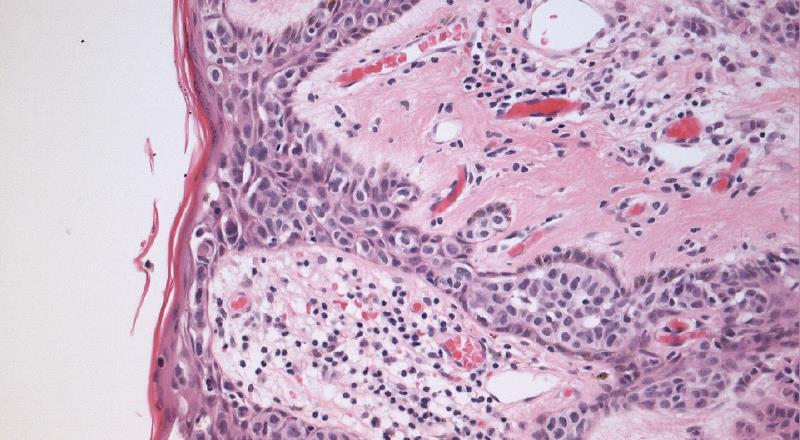

A 63 year old lady presents with nipple erythema and ulceration. A nipple biopsy reveals large round cells with large nuclei, prominent nucleoli and abundant vacuolated cytoplasm within the epidermis. The cells are positive for CK7 and negative for S100. What is the most likely diagnosis?

More frequent in post-menopausal women 1 – 4.3% of all breast cancers Associated invasive carcinoma almost always seen, but rarely (<5%) no carcinoma is found in mastectomy specimens

Defining histologic feature is the presence of malignant glandular epithelial cells within the squamous epithelium of the nipple.

Malignant melanoma Bowen’s disease Clear cell change Toker cell hyperplasia Exclude epidermal infiltration by underlying tumour invading skin

Paget’ s – LMWCK (Cam5.2), CK7, EMA, CEA,

Her2 positive, GCDFP-15, PAS+

Melanoma - S100, melanA, HMB45, SOX-10 positive

Bowen’ s – HMWCK, p63 positive